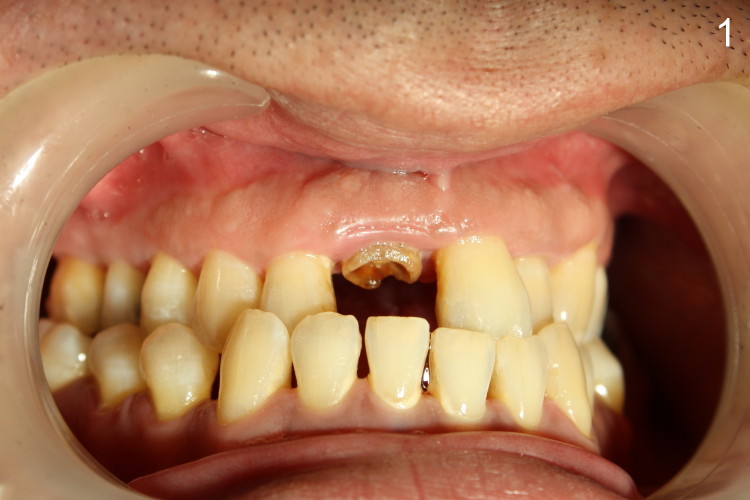

Salvageable or not (2)?

A 37-year-old otherwise healthy gentleman presented to clinic for extraction due to multiple times of crown failure (Fig.1,2). It appears that crown margin is ~2 mm supragingival. After RCT retreatment and fabrication of cast post & core, the tooth seems to be salvageable. But the patient was adamant in extraction and implant restoration.

Finally the tooth was extracted. In fact, it is indeed nonsalvageable. Can you guess what is the main reason for non-salvageability?